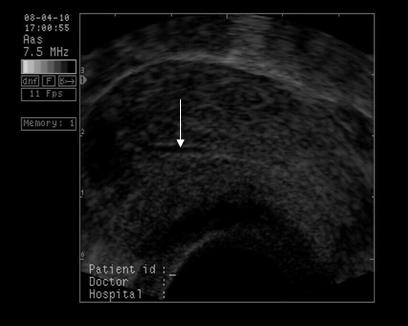

Fig nr 6 Decolare de pol inferior ( cu sageata ) la o sarcina de 7 sapt

Fig. nr. 66. Aceeasi sarcina, ca in figura precedenta, la 12 saptamani , fara imagini patologice la polul inferior ovular, marcat cu sageata

Fig nr. 67 Decolare de pol inferior ovular, situat in continuarea canalului cervical

( sageata) la ecografia transvaginala

Fig nr 68 Decolare de pol inferior la ecografia abdominala ( sageata )